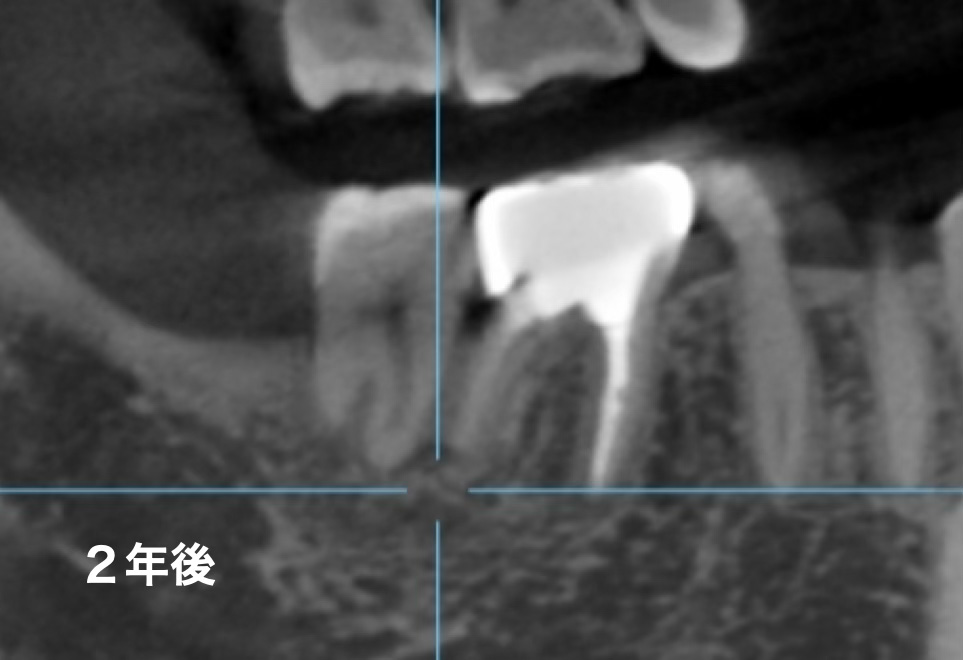

初めの治療から早くも2年以上が経過しました。その経過を確認するためにCTを撮影しました。初診時の矢印部分を見ていただければおわかりいただけると思いますが、透過像がなくなり、骨がしっかりと再生して治っているのがわかります。

2年経過した時点でも違和感なく、日常生活に不便を感じておらず、精密根管治療とジルコニアクラウン治療で歯を残すことができ患者さんのQOL(生活の質)を維持できたことが医療人としてお力添えできたと感じられました。